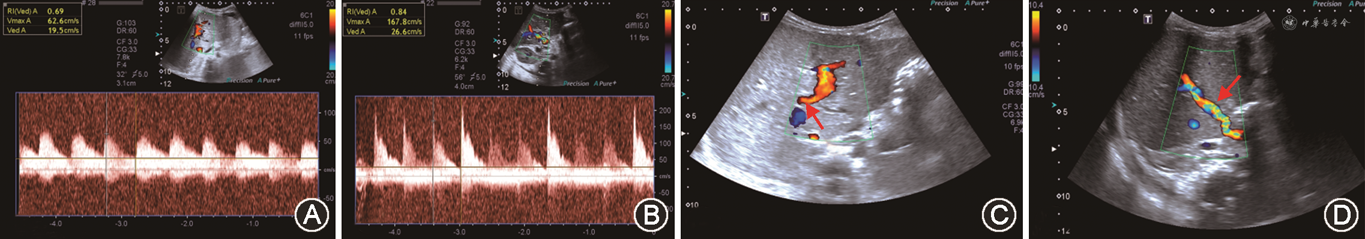

1. 评估内容:主要评估移植肝肝动脉、门静脉、肝静脉、下腔静脉吻合口及其近、远端血流情况,判断是否存在血管痉挛、扭曲、狭窄、血栓等异常情况(图5)。

2. 观察要点:(1)术中超声检查发现门静脉周围搏动性肝动脉血流信号消失或显示不佳,吻合口远端肝内动脉峰值流速<20 cm/s时,在排除血管痉挛后,要考虑到肝动脉急性血栓形成、吻合口狭窄、扭曲或血管成角等可能;(2)术中超声需测量吻合后门静脉血流速度和血流量,流量过高(>250 ml·min-1·kg-1),术后有小肝综合征风险的可能,过低可能存在门静脉侧支分流血管。

(1)肝动脉:通常在移植肝第一肝门区检测肝动脉血流,肝右动脉可于肝内门静脉右支前方测量;肝左动脉可于门静脉左支矢状部旁测量(图8A)。移植术后肝动脉收缩期峰值流速(peak systolic velocity,PSV)变动范围较大,术后第一天PSV值可为19~133 cm/s[39, 40]。肝动脉RI正常范围为0.55~0.80,收缩期加速时间(systolic acceleration time,SAT)<0.08 s[41]。需注意的是,肝移植术后早期,肝动脉RI可较高,甚至可达到1.0,可能与术后血管痉挛、受体年龄偏高及供肝冷缺血时间过长等因素有关。对移植肝动脉RI异常患者应严密动态观察,结合患者病史、临床表现及其他影像学检查结果诊断及鉴别移植肝并发症[42]。评估流程如图7所示。

(2)门静脉:移植肝门静脉血流频谱呈向肝持续性单相波,血流流速可随呼吸轻微波动(图8B)。肝移植术后早期,门静脉流速有明显增高现象(PSV最高可达100 cm/s),甚至可以出现湍流,多数情况下会于3个月左右逐渐下降。这种移植术后早期门静脉流速增高的表现属正常现象,应注意与吻合口狭窄造成的流速增高相鉴别[43]。

(3)肝静脉及下腔静脉:正常肝静脉频谱具有期相性,反映血流随心动周期不同的生理变化(图8C)。可在距第二肝门2 cm内测量各支肝静脉流速及观察频谱形态,肝静脉流速变化范围较大(20~100 cm/s),多为三相波频谱。下腔静脉近心端流速曲线多为三相或双相波,少数呈单相波,流速变化范围大(30~100 cm/s)。